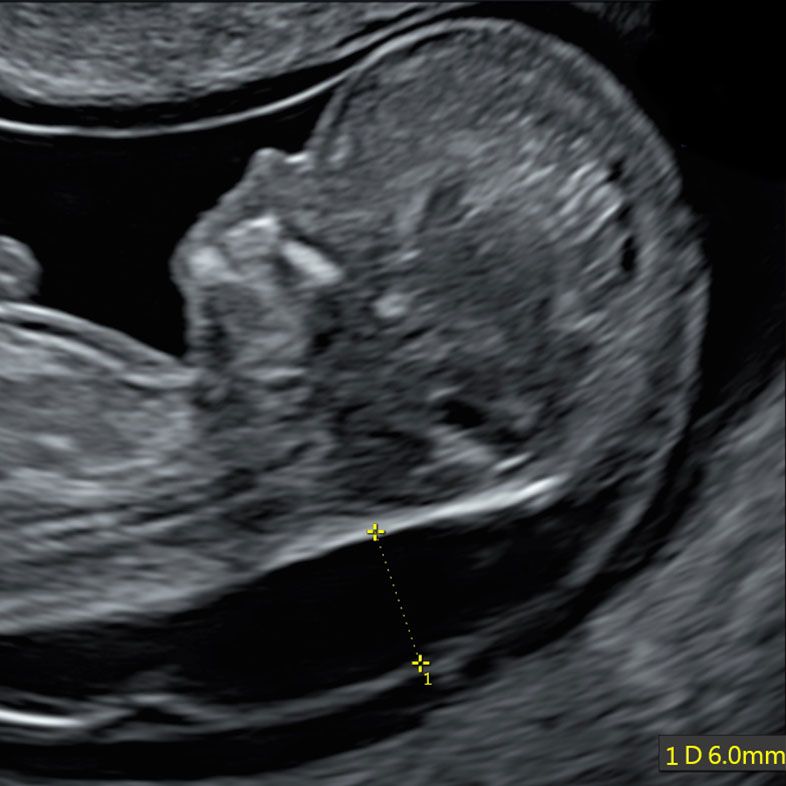

Baby with increased NT (6.0mm vs 3.5mm cutoff) and severe heart defect diagnosed by Early Fetal Echocardiography at 12 weeks

With the Early Fetal Echocardiography at 12-13 weeks the fetal heart is about the size of corn grain, however with our advanced ultrasound technique we will check position of the heart and stomach, presence and size of all four chambers, presence and size of two great arteries and their positions. We also will check the blood flow inside the heart and on cardiac valves by advanced Colour Doppler technique.